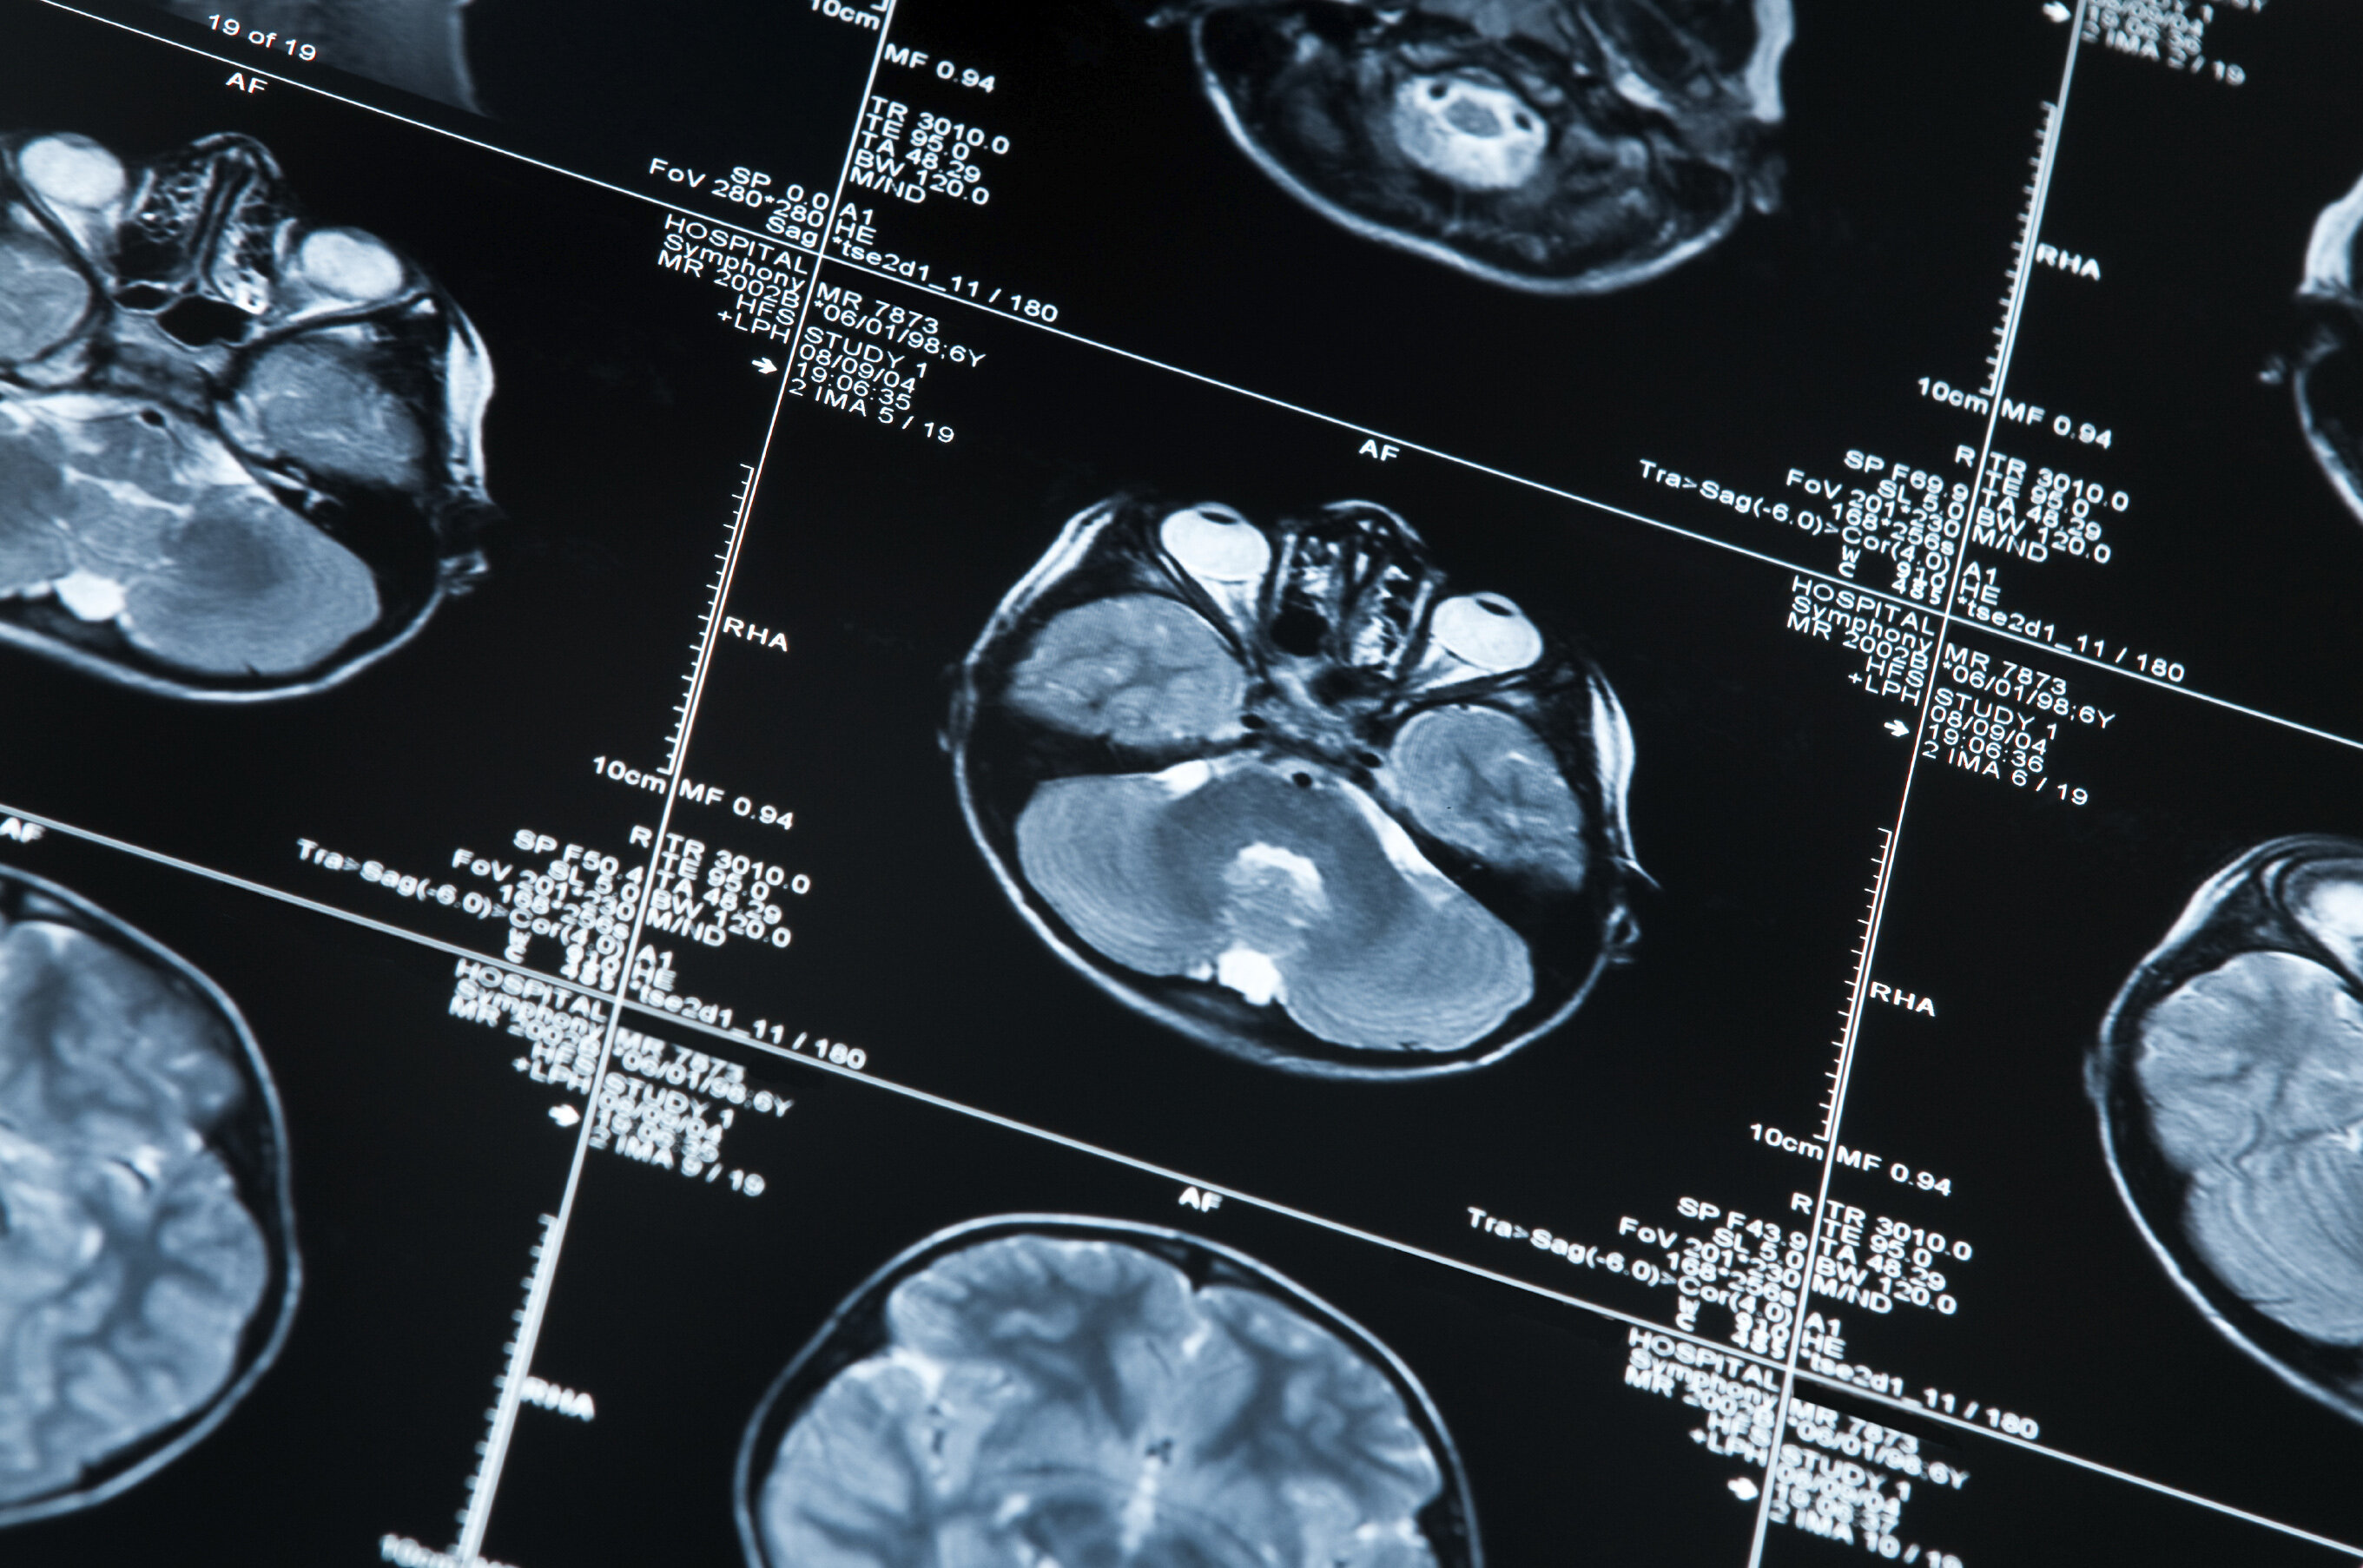

Recently completed EMPIR project Innovative measurements for improved diagnosis and management of neurodegenerative diseases (15HLT04, NeuroMET) developed reference measurement procedures to accelerate the uptake of minimal invasive methods for the early diagnosis and monitoring of the progression of neurodegenerative diseases such as Alzheimer’s and Parkinson’s. The research explored innovative techniques for early diagnosis and monitoring, based on non-invasive blood and saliva tests, in-vivo magnetic resonance approaches and cognitive assessments.

- A database of blood, saliva, cerebrospinal fluids, magnetic resonance imaging and spectroscopy diagnostic biomarker data collected from the NeuroMET patient cohort and combined through new mathematical models to help improve the accuracy of Alzheimer’s disease diagnosis. The studies carried out in the follow on project Metrology and innovation for early diagnosis and accurate stratification of patients with neurodegenerative diseases (18HLT09, NeuroMET2) will enable further improvement of the methods for early diagnosis and patient stratification. A NeuroMET stakeholder workshop will be held in Berlin in summer 2020 to increase engagement with clinicians and disseminate those findings

- An abstract entitled ‘Product ratios of metabolite concentration as potential Alzeihmer disease biomarkers‘ was awarded an Magna cum laude award, meaning it was rated among the top 15% out of more than 5000 abstracts, at the 27th Annual Meeting of the ISMRM (International Society for Magnetic Resonance in Medicine) held in Montreal in May 2019.